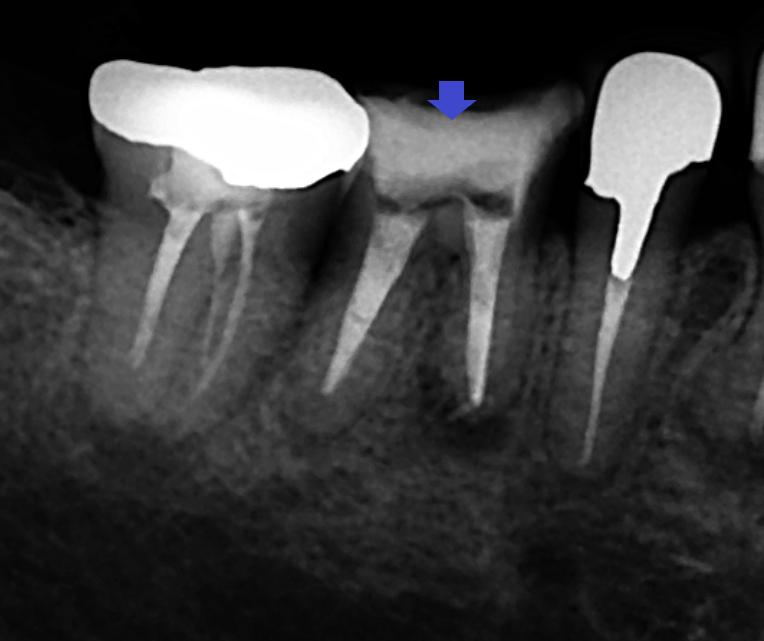

まずは、すでに根管治療が開始されていた下顎第一大臼歯の精密再根管治療を行いました。画像は、下顎第一大臼歯の根管充填のレントゲン写真です。下顎第一大臼歯の再根管治療を終えても歯茎の腫れは改善しませんでした。その後、下顎第二大臼歯の根管治療を開始したところ歯根破折が確認され、保存不可と判断し抜歯をしたところ歯茎の腫れは消失しました。